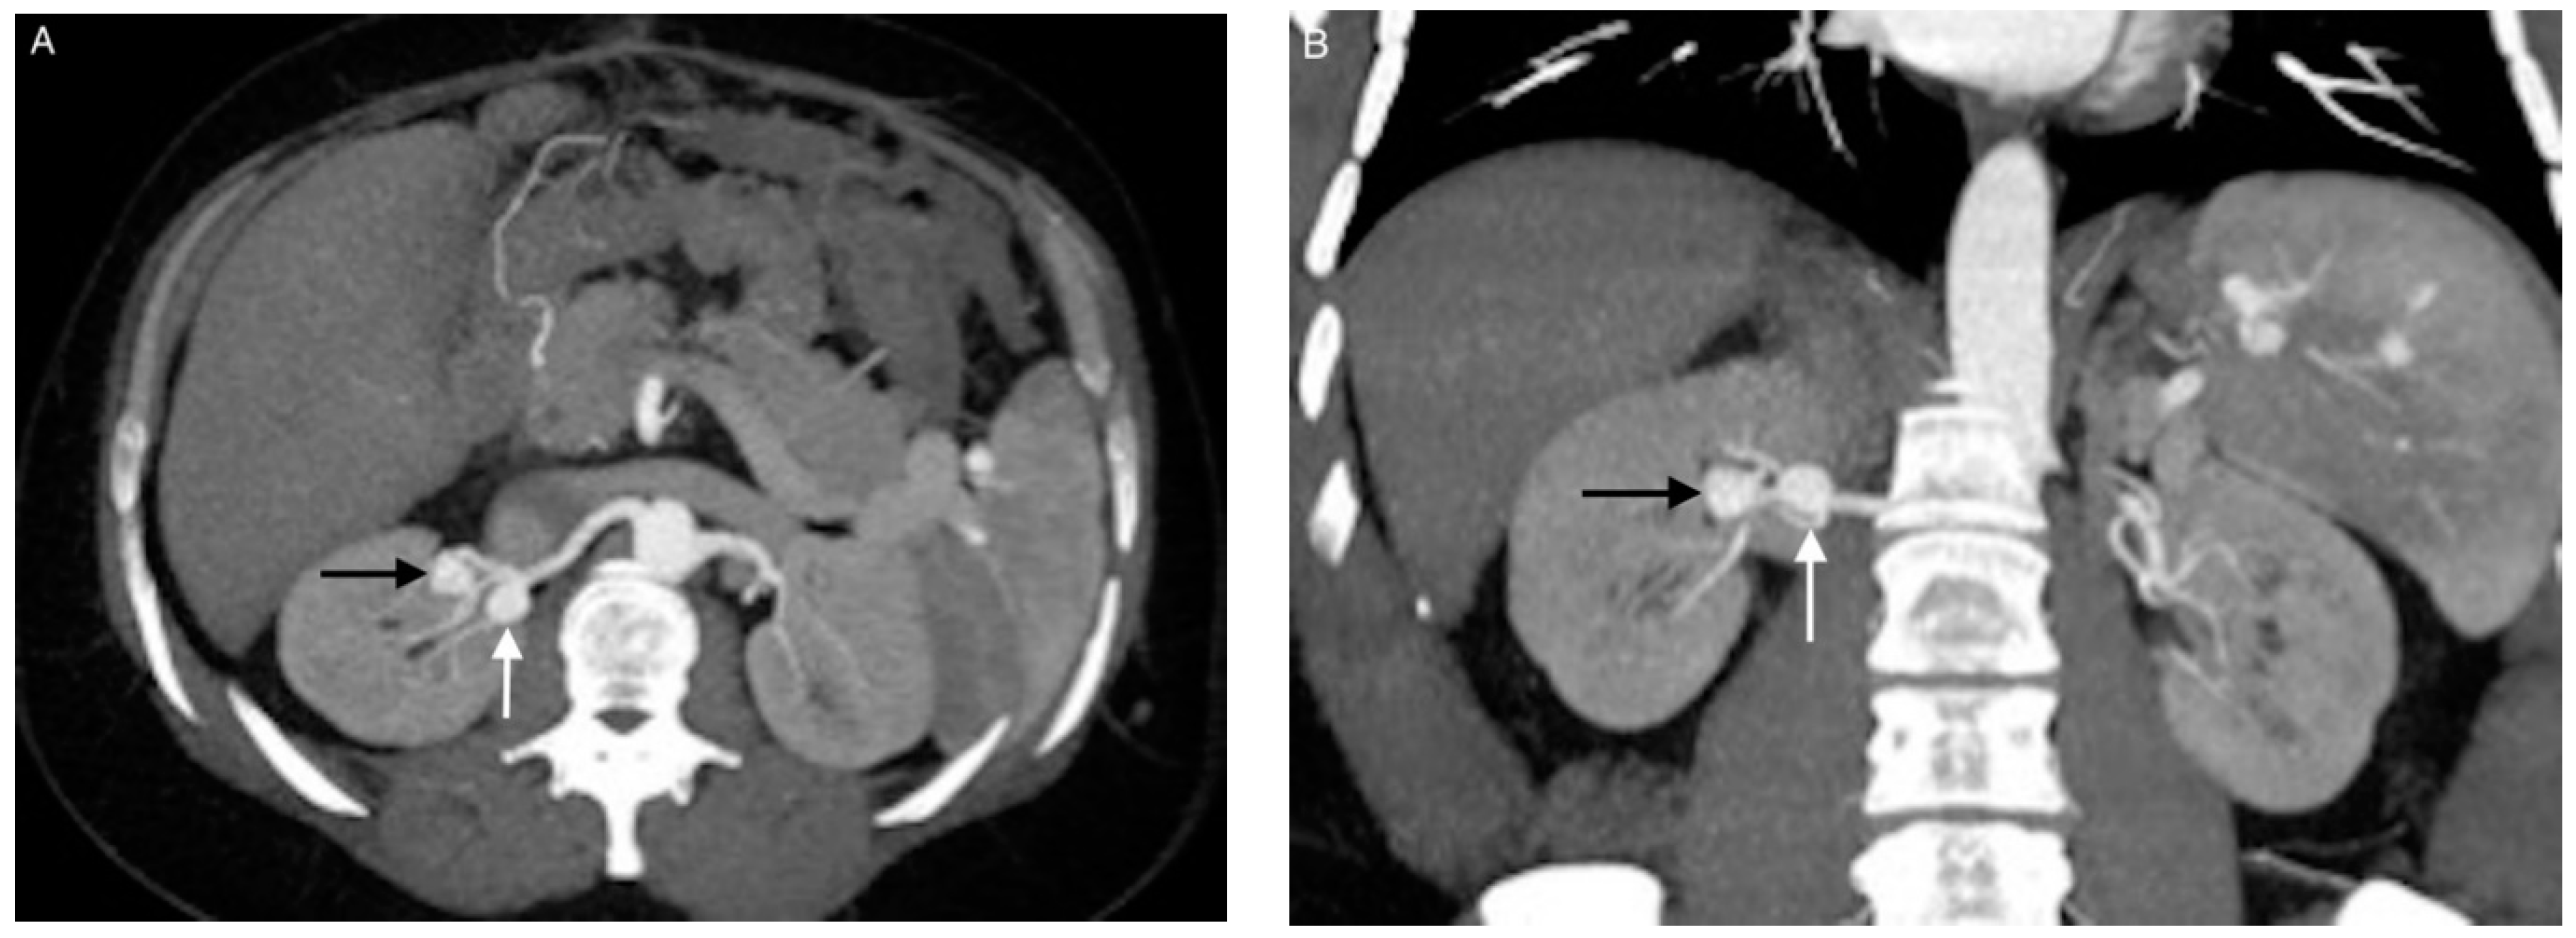

3.3. Coil Embolization and Outcomes